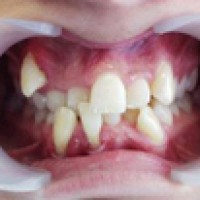

Sâu răng/vỡ răng không chỉ gây hôi miệng, mất vệ sinh mà còn ảnh hưởng đến thẩm mỹ răng. Với các trường hợp sâu răng nặng không điều trị nội nha không hàn răng được sẽ phải nhổ răng để tránh mất vệ sinh

Răng sâu được chia làm nhiều mức độ khác nhau và không hẳn cứ răng nào bị sâu thì phải nhổ bỏ. Thực tế có những trường hợp răng sâu được khôi phục và bảo toàn khá tốt giúp người bị răng sâu